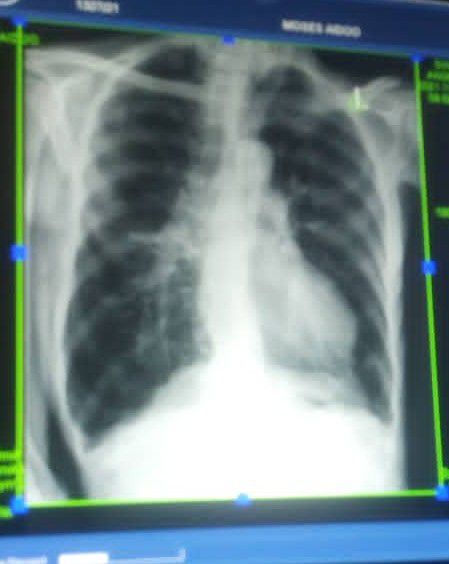

Case study

Pleural

Pneumology